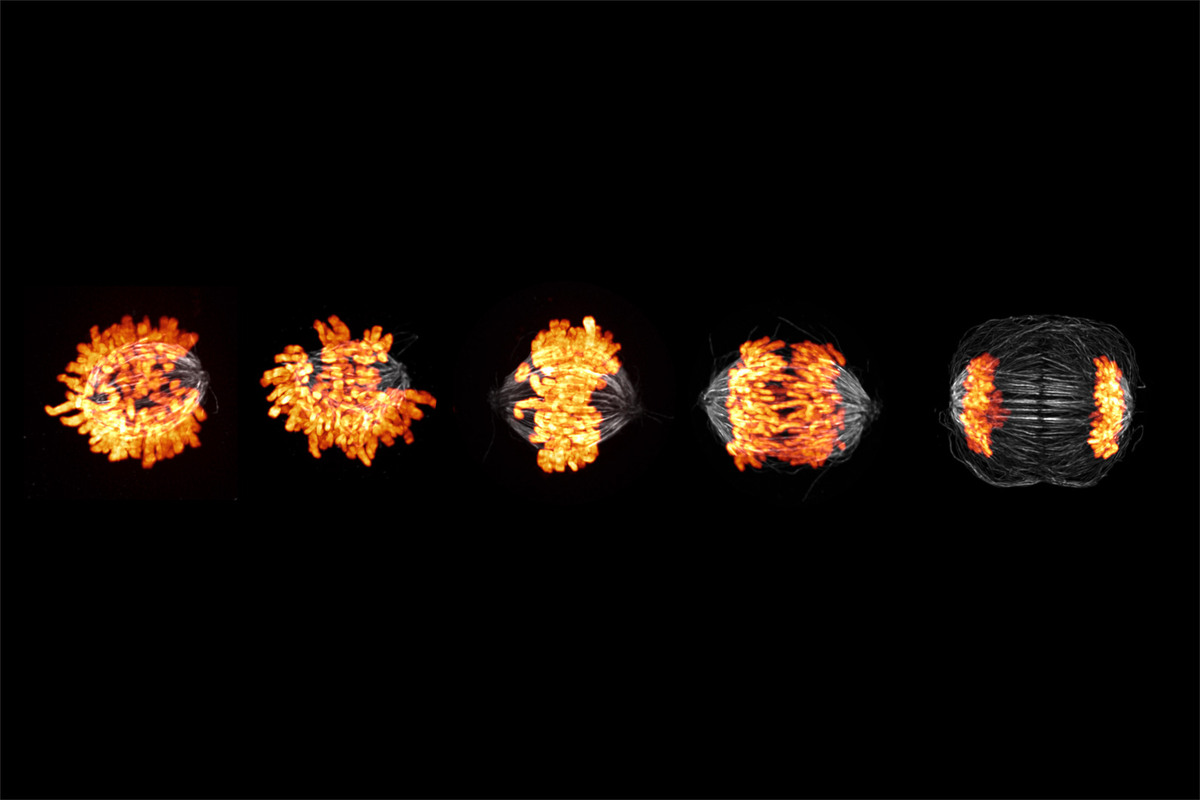

9. Ανθρώπινα κύτταρα σε διάφορα στάδια της μίτωσης

Στην παραπάνω εικόνα βλέπουμε ανθρώπινα κύτταρα σε διάφορα στάδια της μίτωσης, διαδικασίας κατά την οποία τα αντιγραμμένα χρωμοσώματα διαχωρίζονται σε δύο νέους πυρήνες. Με πορτοκαλί χρώμα διακρίνονται τα χρωμοσώματα και με λευκό οι μικροσωληνίσκοι, οι οποίοι παρέχουν δομή και σχήμα στα ευκαρυωτικά κύτταρα. Η εικόνα ανήκει στον Δρ. Andrew Moore.